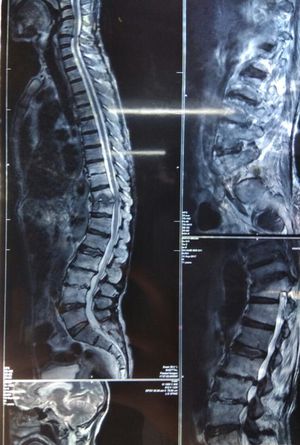

Cord compression at multiple level

Cord compression at multiple level,C4- C5,L3-L4,L3-L2,D11-D10. Loss of disc spaceC3-c4, D10-11, L4-3. Destruction of body of D10,D11... DD:Potts disease, Degenerative dissease, Secondaries in vertebra Multiple myeloma.